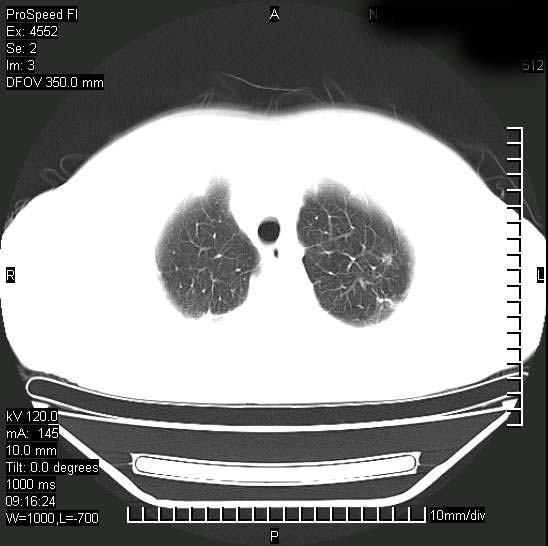

标题: CT15528:女性,79岁,近几日晚上高热,39度,仍咳少量血

十几年前曾患肺结核,一周前突咳血约100ml,中性粒细胞稍高,诊断两上肺陈旧结核,下肺炎症,给予抗炎治疗,近几日晚上高热,39度,仍咳少量血,4天前ct及今天ct上传。

[face=黑体]8月30日[/face]